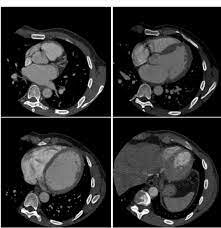

Se introdujo la Tomografía por rayo de electrones EBCT ( del ingles Electrón Beam CT). EL EBCT utiliza una arquitectura estacionaria (sin rotación), donde un rayó de electrones hace un barrido a lo largo de cuatro placas semicirculares que rodean al paciente. Tenían una alta resolución temporal adquiriendo hasta 60 cortes por segundo.

• 1980 - Quinta Generación

1980 - Quinta Generación